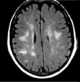

Anderson syndrome